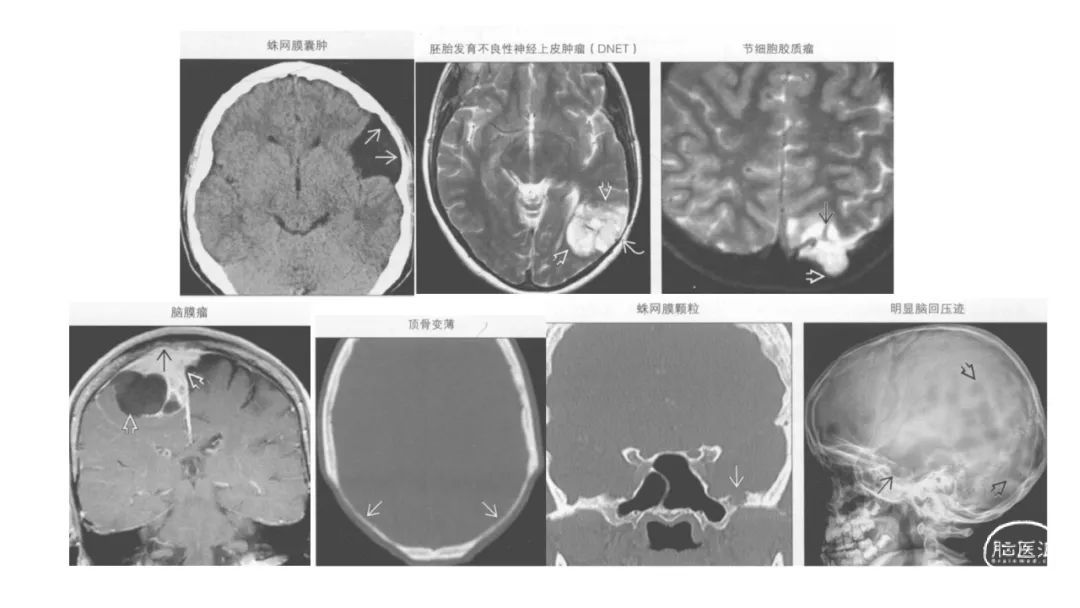

颅脑影像诊断基础知识讲座:颅骨病变